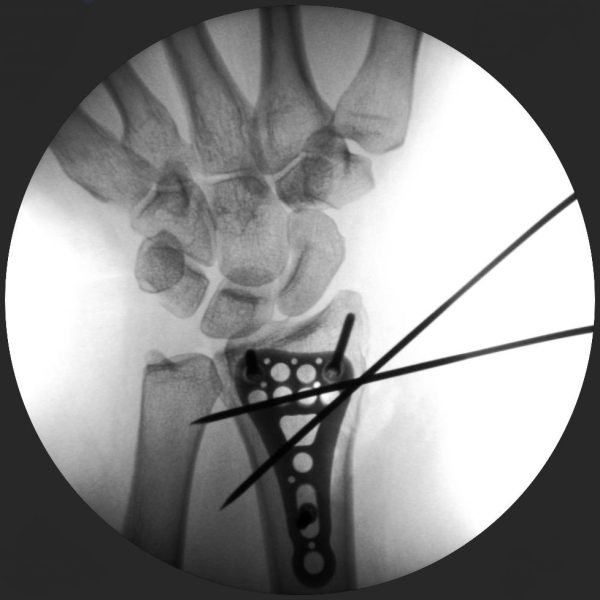

Skan-C plays a critical role in orthopaedic procedures, providing excellent imaging during interventional procedures, and allowing for precise localization and accurate treatment. The ability of Skan-C to offer dynamic visualization of visualization structures enhances patient safety, minimizes complications, and improves the overall effectiveness of orthopedic interventions.

CRIF - Closed reduction internal fixation

ORIF - Open reduction internal fixation

High-quality imaging

Skan-C uses advanced imaging technology, such as pulsed fluoroscopy and digital subtraction angiography, to provide highly detailed images of the affected area. This allows doctors to perform procedures with increased precision and accuracy, and better patient outcome